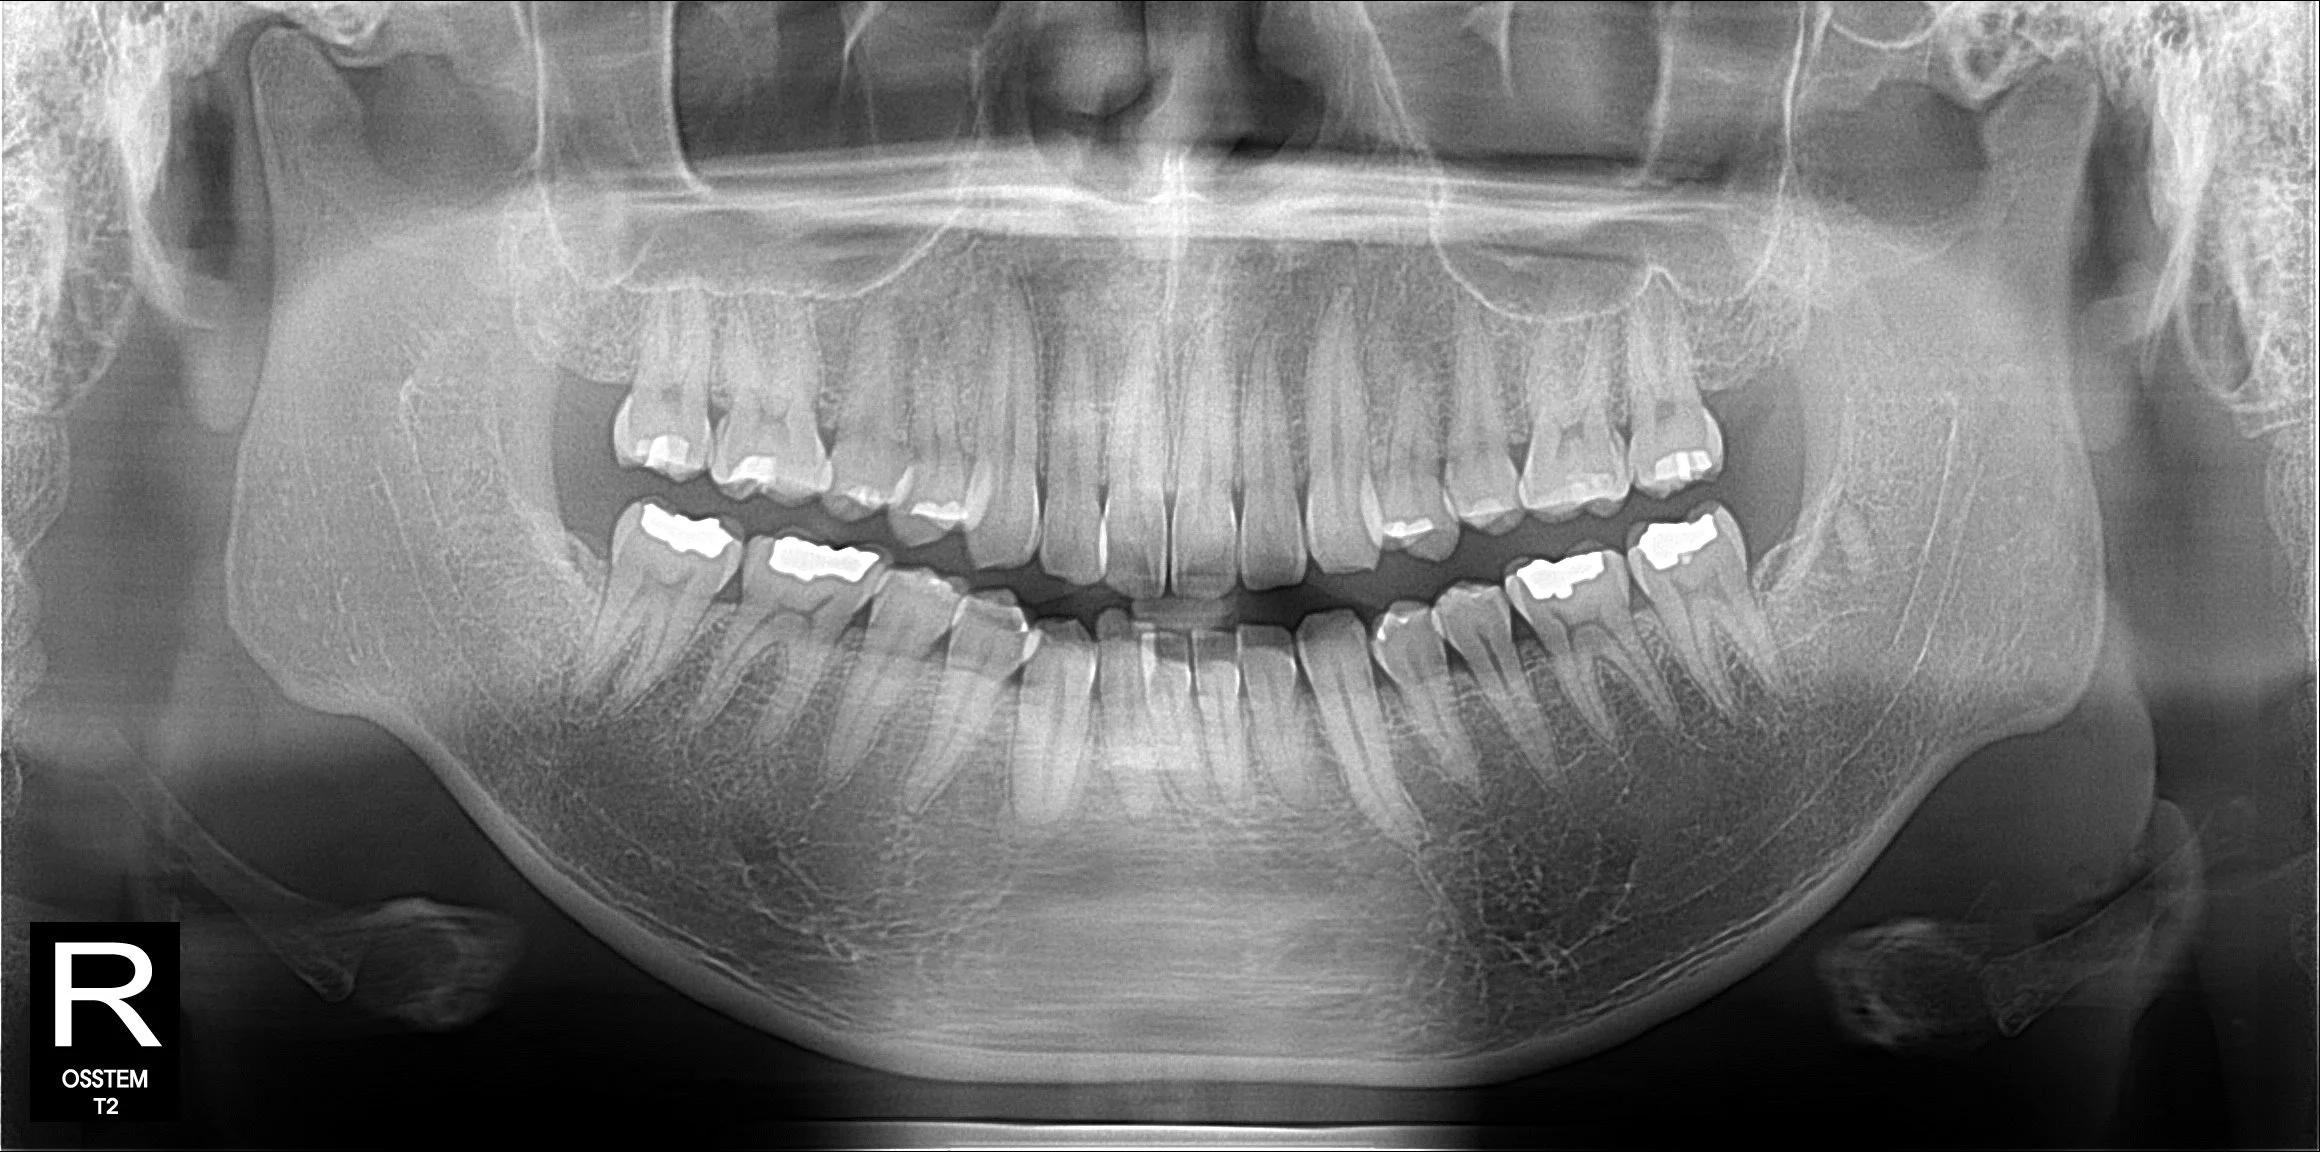

CBCT 연동 시스템: CBCT 데이터를 활용해 잇몸뼈 속 치아 뿌리(치근)의 형태와 위치를 3차원으로 파악합니다. 뿌리의 이동 경로까지 미리 계산하여 더욱 안전하고 정교한 치료 계획을 세웁니다.

눈에 보이는 치아 머리(치관)뿐 아니라 이제 치아 뿌리(치근)까지 확인이 가능하고 시뮬레이션이 가능해졌습니다.

투명교정 치료 전

투명 교정 치료 1년 경과 후